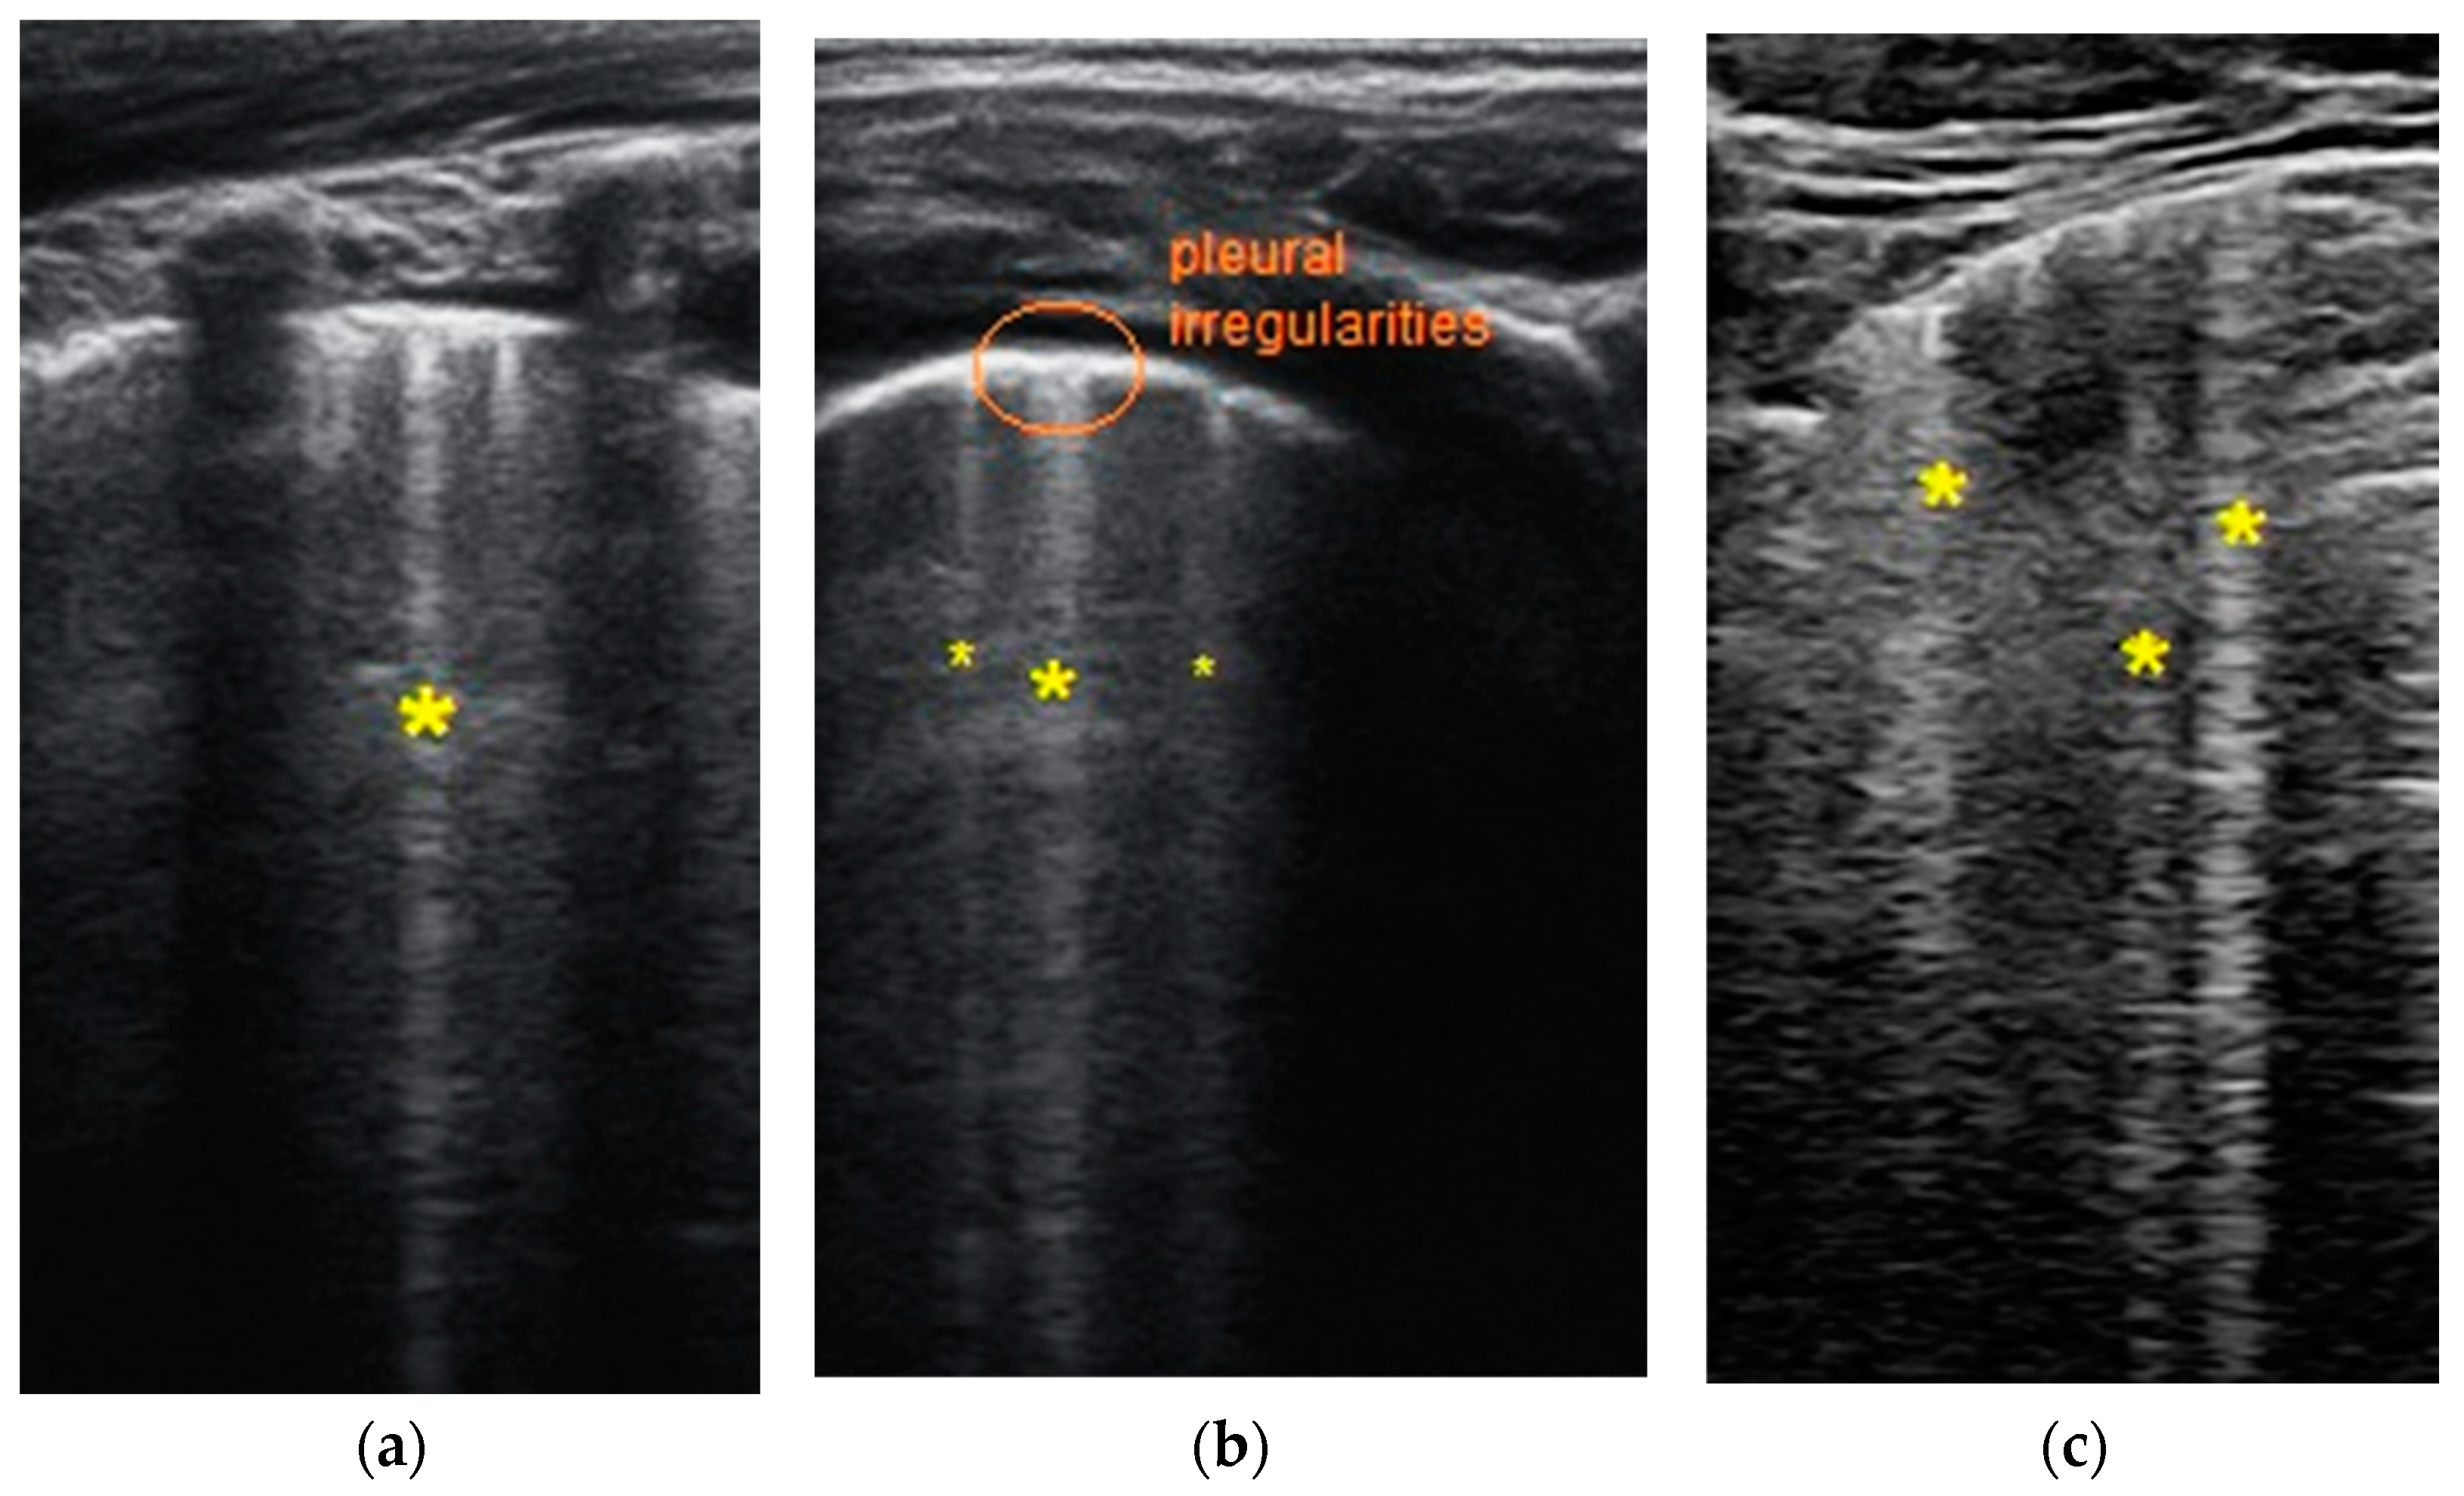

- Transverse physiologic A-lines that depict healthy parenchyma;

- Isolated/sparse vertical B-lines are equivalent to interstitial edema;

- Confluent vertical B-lines correspond to alveolar edema;

- Subpleural/peripheral consolidations;

| Normal/physiological A-lines | More than 2 B-lines (sparse B-lines) with associated pleural abnormalities | Coalescent or confluent B-lines | Large peripheral consolidation (wider than 1 cm) in association or not with air bronchogram |

| One or two B-lines per intercostal space | ‘White-lung’ aspect or small peripheral consolidation (smaller than 1 cm) |